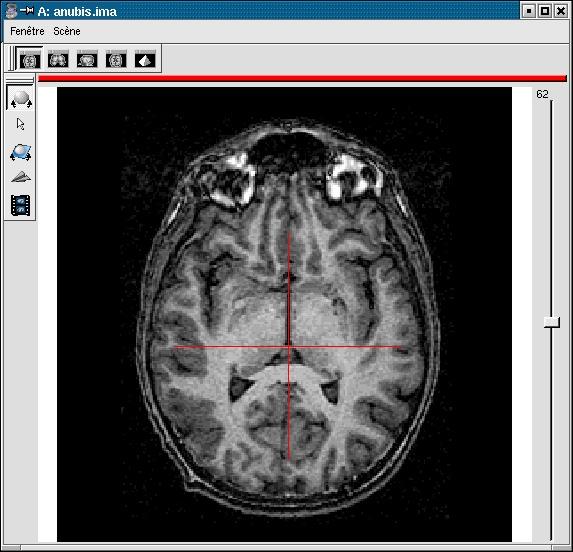

If your image is not spatially normalised, Anatomist will help you to click on the 3 or 4 points of interest.

- If the volume is not already visible, click on the edit button of one of the point parameters to have Anatomist display it

- Set the Anatomist view so as to see the point (use the slice slider) and click in it on the wished point.

- When the cursor position is good, click on the button of the 3D point in BrainVISA: the position is transfered from Anatomist to BrainVISA.

- If you are not happy with the position, you can restart the operation: click again on other points then on the parameter button to validate: a new position replaces the previous one in BrainVisa.

You have to select 3 points (you can use a sagittal slice if you prefer):

- Intersection of anterior commissure with interhemispheric plane;

- Intersection of posterior commissure with interhemispheric plane;

- Any point of the interhemispheric plane not aligned with the previous ones.

- Optionally, any point of the left hemisphere. Specifying this point is not mandatory, it is only useful to detect a possible orientation problem on the input image. Be careful, axial and coronal views in Anatomist are in radiological convention by default (left and right are flipped).

Posterior commissure: